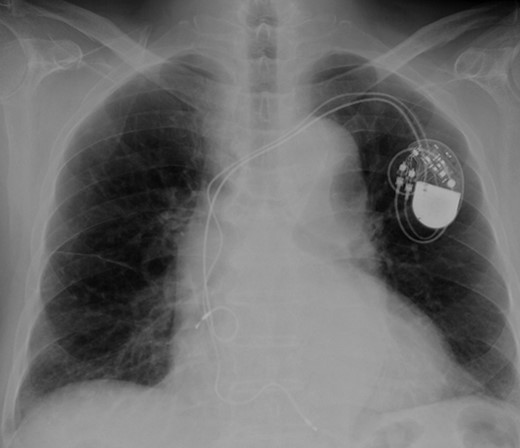

Eight years ago, a DDD pacemaker was implanted in an elderly man due to complete atrioventricular (AV) block. The pacing sites were the appendage of the right atrium and the apex of the right ventricle (Fig. 1) subsequently he suffered PICM with an LV ejection fraction of 37% and obvious dyssynchrony. He had chronic heart failure of NYHA II. Suddenly, the patient developed fever and complained of difficulty eating. Transthoracic echocardiography showed a vegetation (11 × 12 mm2) at the pacemaker leads, and this vegetation was also attached at the tricuspid valve (Fig. 2). Laboratory examination showed elevated white blood cell count and C reactive protein levels. He was diagnosed with PAIE, although the peripheral blood cultures showed no bacteria. After antibiotic therapy, laboratory examination showed decreasing inflammation parameters, but the size of the vegetation remained stable.

According to the current guideline for pacemaker infection, it was decided to remove the whole pacemaker system, including the two leads. Since implantation of new transvenous leads seemed undesirable because of ongoing active endocarditis, it was decided to implant epicardial leads on the left atrium and left ventricle via a left mini thoracotomy. Because the patient had complete AV block without any spontaneous R wave, a new DDD pacemaker system was implanted first. The atrial lead was implanted on the appendage of the left atrium, and the ventricular lead was implanted onto the lateral wall of the left ventricle near the first obtuse marginal branch (Fig. 3). The old infected pacemaker system was then explanted by percutaneous extraction.